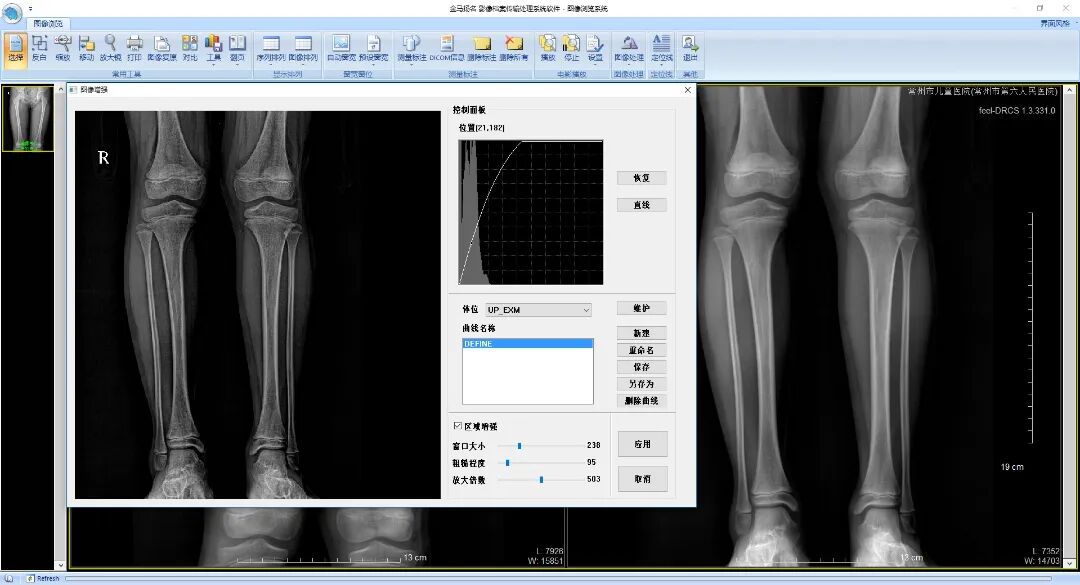

• 图像增强功能(选配)

图片